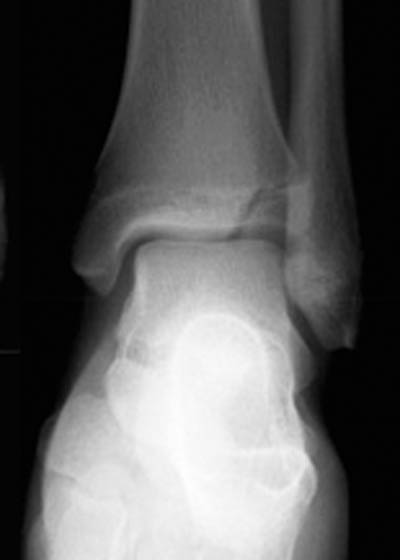

28) Name the abnormality shown in the image below.

29) Give the specific name for the fracture type shown in the image above.